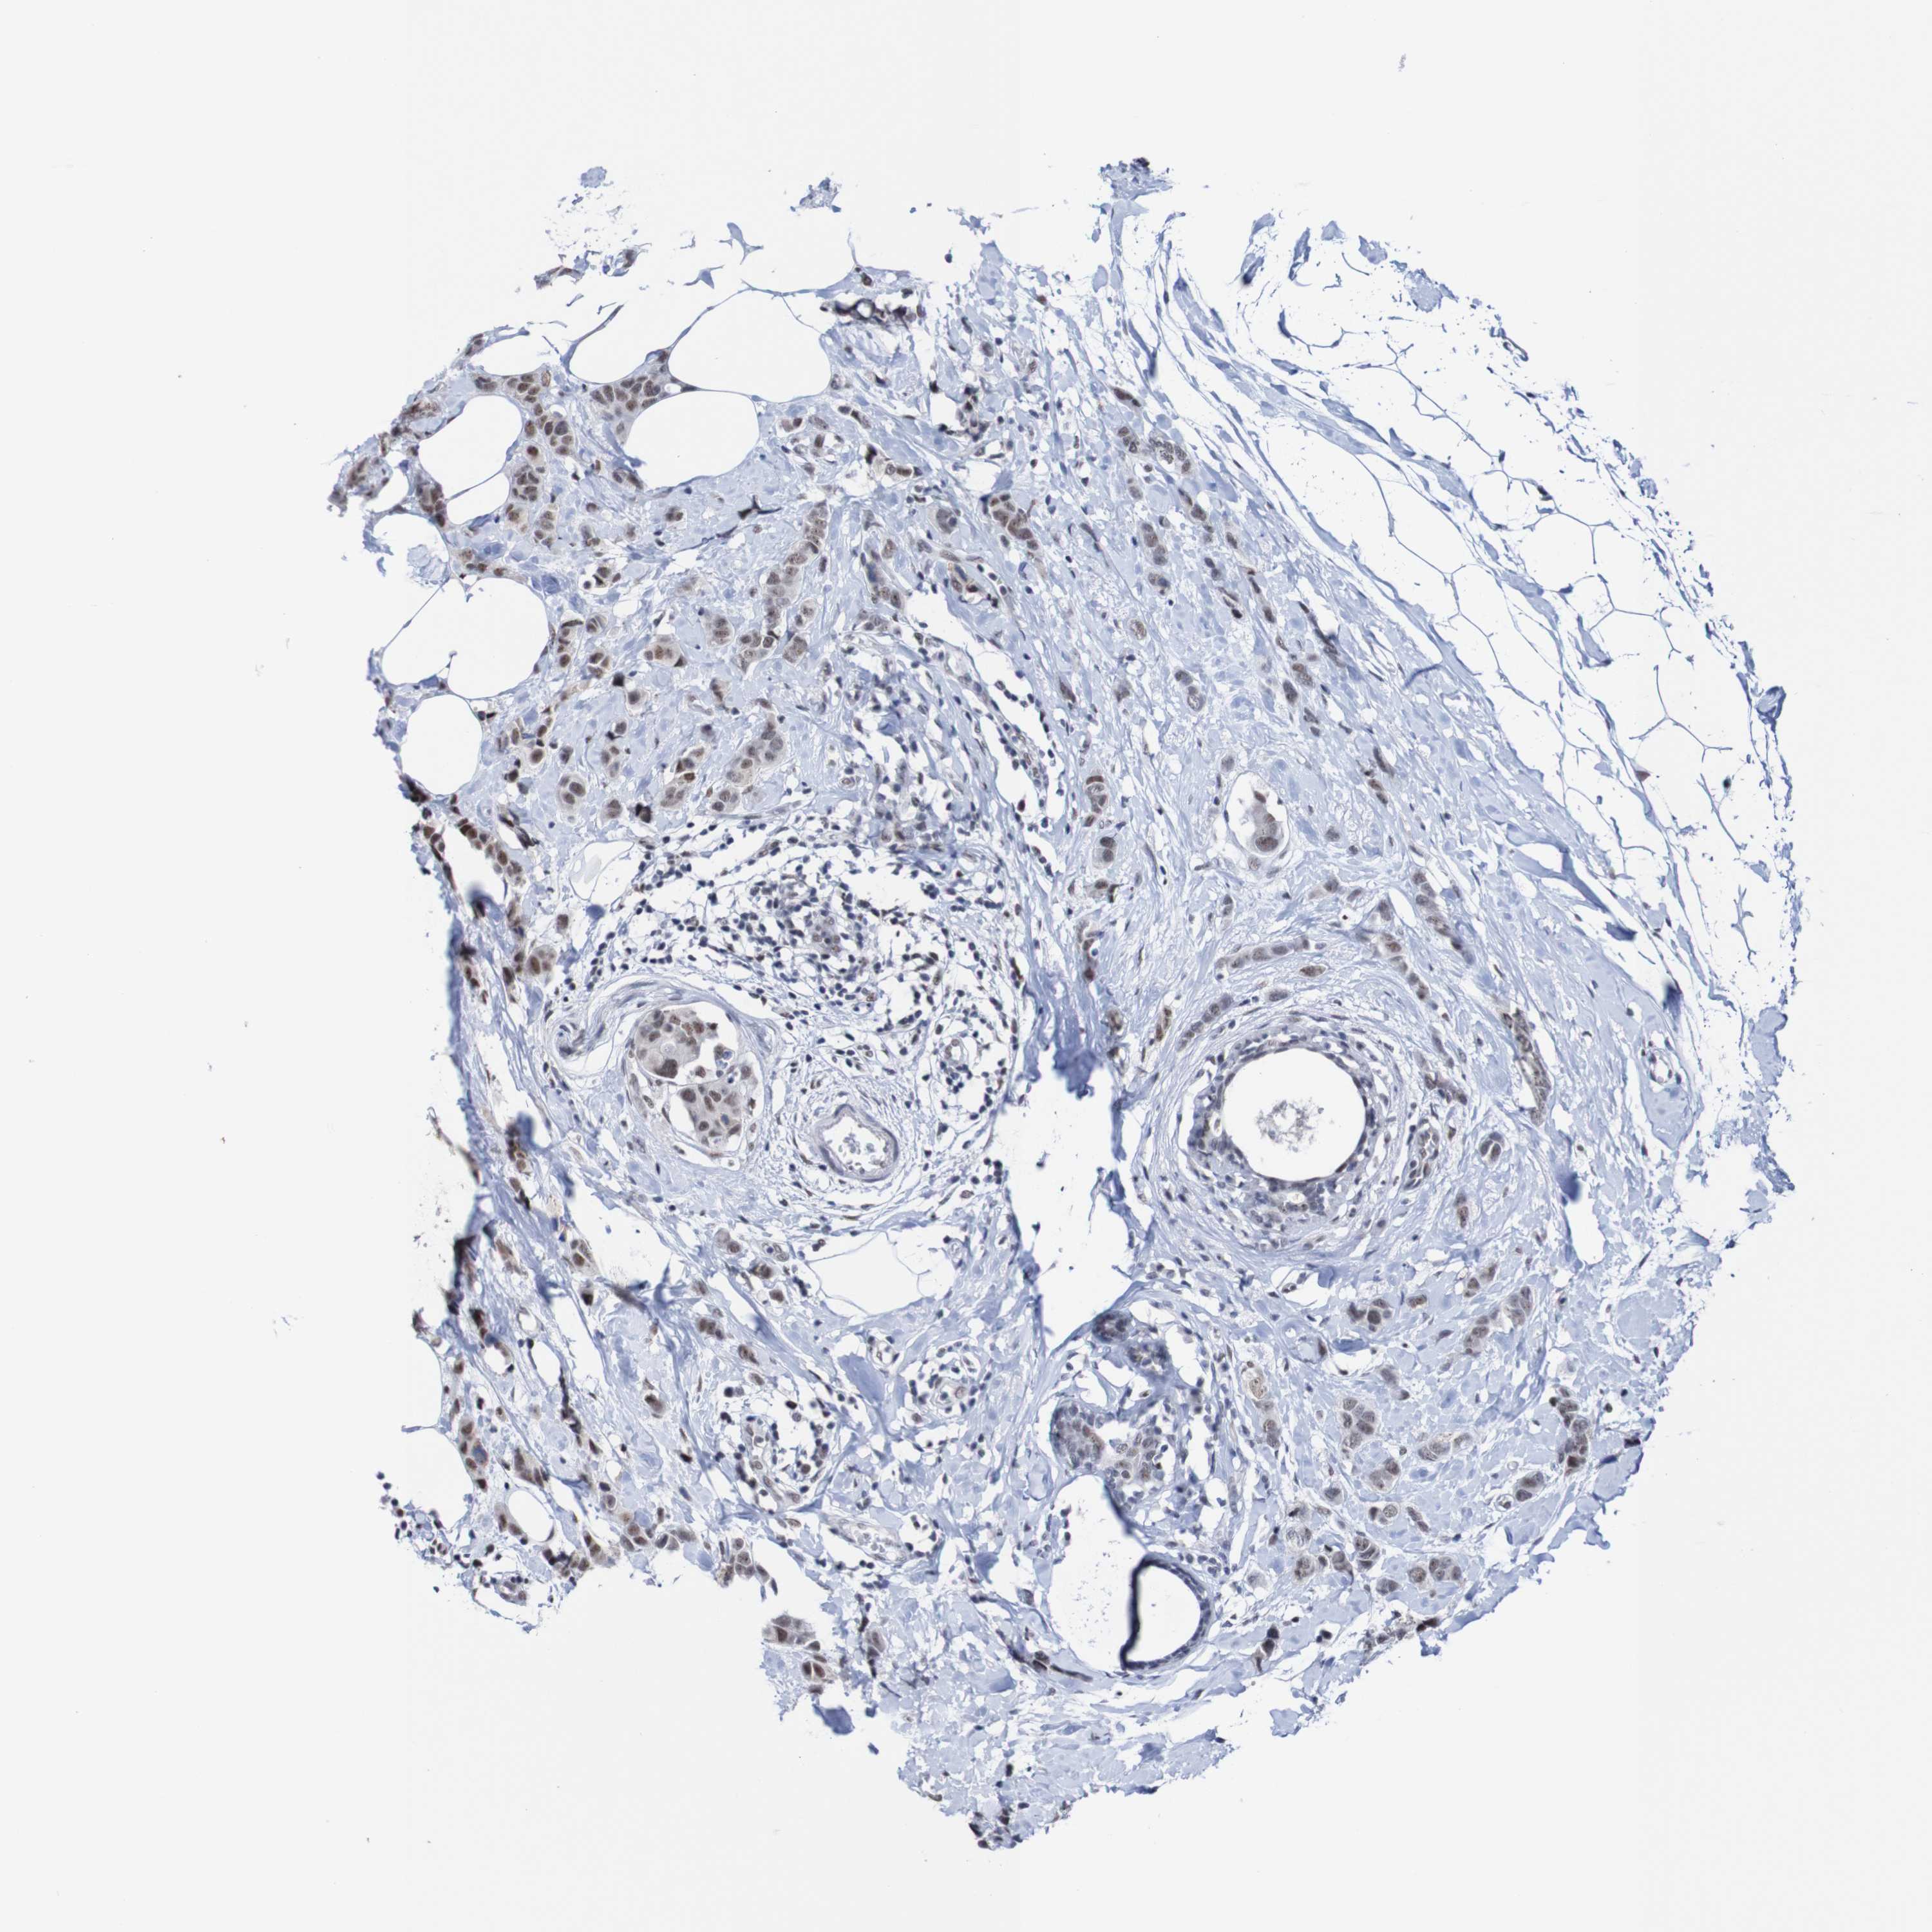

CANCER BREAST CANCER Show tissue menu

BRCA TCGA BRCA VALIDATION PROTEIN EXPRESSION